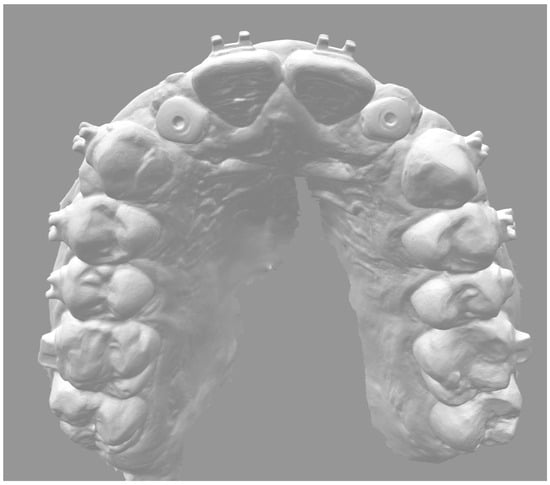

2. Materials and Methods

- 11–12 months: prosthetic finalization and baseline control (T0);